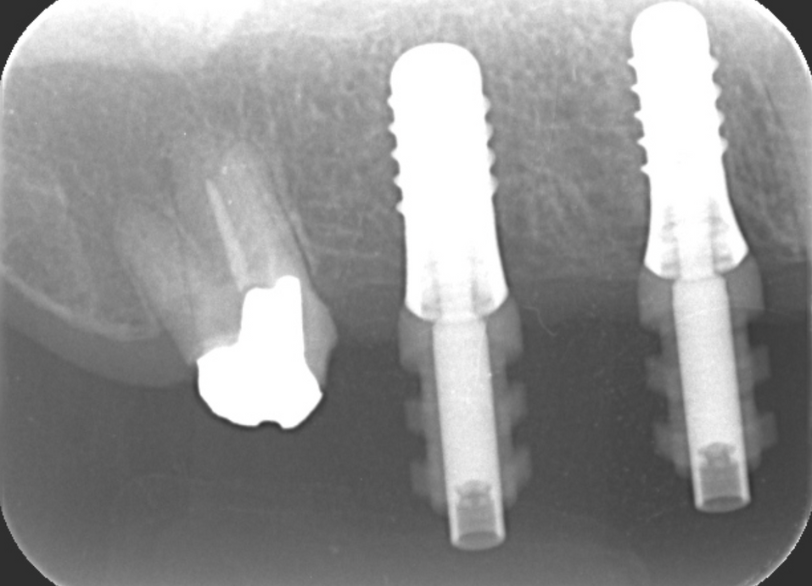

③インプラントを埋入し仮歯装着

顎堤の吸収がなくインプラントを行うにあたり十分な骨が得られた

③インプラント上部構造装着